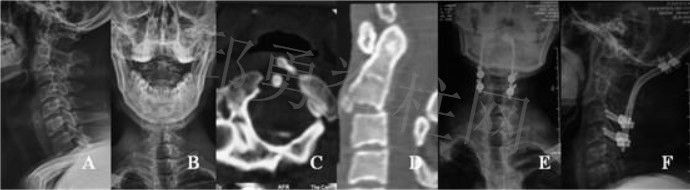

#5820 男,42岁,T5,T6,T7爆裂性骨折伴不全瘫。X线侧位片显示T5-T7压缩性骨折(Figure A)。CT清晰骨折部位和骨折块移位方向(Figure B,C, D,E)。

患者接受后路T6-T7全椎板切除减压sino固定融合术(Figure F,G)。